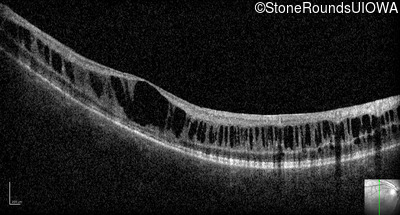

Optical Coherence Tomography - Left - 10/40

Exemplar / OCT Stack